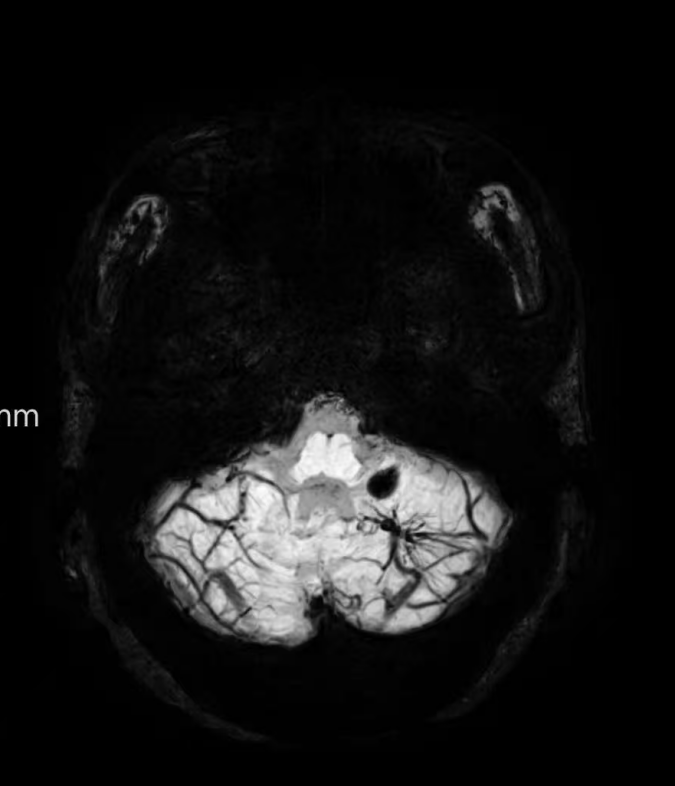

臨床中遇到一位患者,中年女性,反復(fù)出現(xiàn)頭痛,時輕時重,常規(guī)CT及磁共振檢查無明顯異常發(fā)現(xiàn),最后建議加做一個磁共振磁敏感加權(quán)成像(SWI),結(jié)果發(fā)現(xiàn)是左側(cè)小腦發(fā)育性靜脈畸形(DVA),SWI清晰顯示畸形的靜脈及周圍含鐵血黃素沉積;如下圖。這正是她頭痛的原因。

①診斷靜脈畸形:SWI能高精度地顯示發(fā)育性靜脈畸形——一種常見的腦血管畸形。在SWI上,發(fā)育性靜脈畸形會呈現(xiàn)典型的“海蛇頭”或“水母頭”征,即一堆細小的髓靜脈匯入一支粗大的引流靜脈。